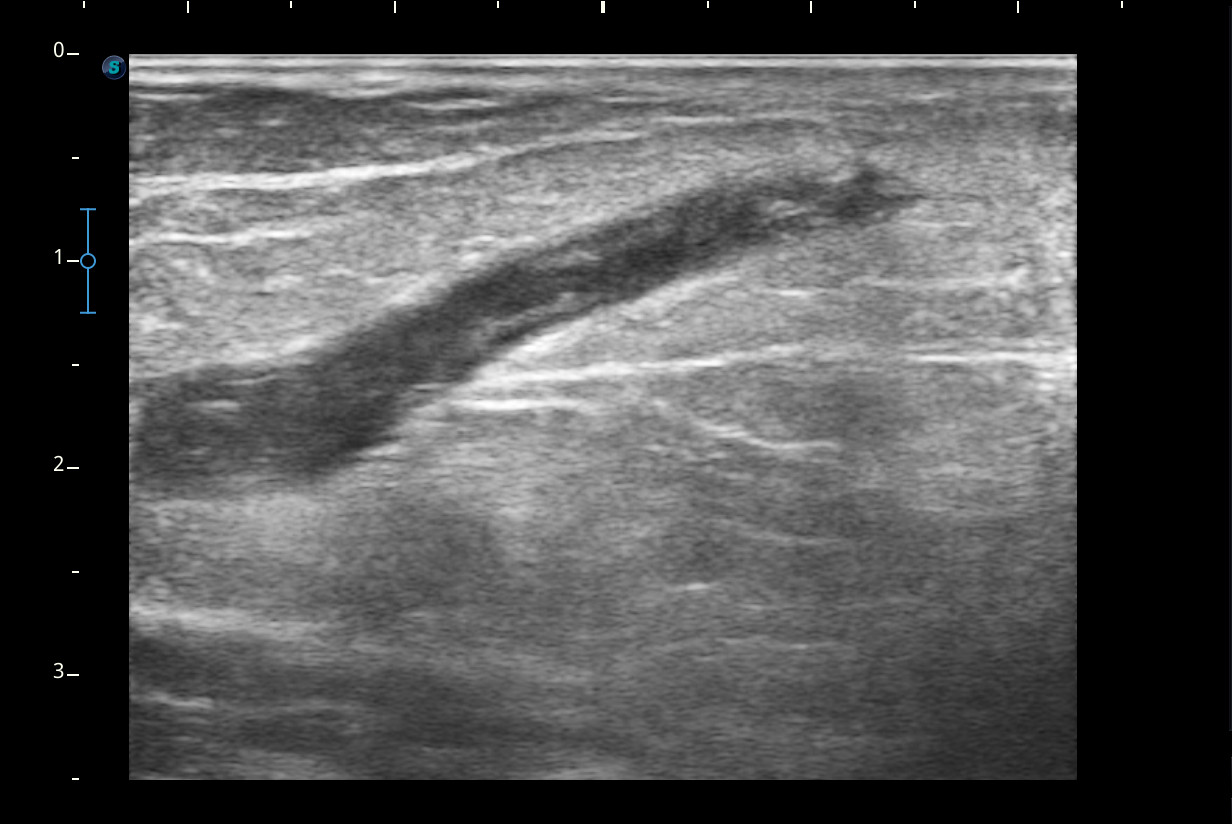

Se visualiza congestión del tejido subcutáneo del brazo y ocupación de la luz de la vena basílica del brazo por un trombo.

Diagnóstico: trombosis venosa de la vena basílica del brazo derecho. Concordancia con el hospital en el segundo tiempo que acude la paciente.